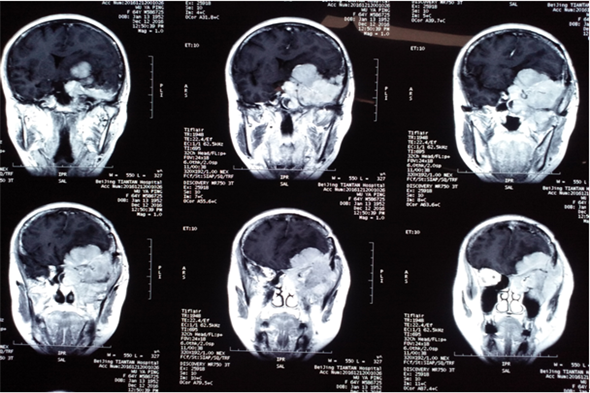

对于患复发性脑膜瘤的吴女士来说,这个冬天注定难以平静,说起吴女士的患病经历,还要从两年前说起,两年前,患者发病就诊于外地医院,头核磁共振检查诊断:颅内占位。随即行开颅手术,术后病理示脑膜瘤,患者恢复较好,未行放射、化疗等辅助治疗。术后一年复查时发现肿瘤再次复发。自觉左眼有发胀感,继之出现左眼突出,视力下降,同时伴有头部疼痛、进食差,随着病情进展,患者左眼视力完全丧失,当即在北京就医,行头MRI检查,结果显示为侵袭性脑膜瘤,肿瘤直径9cm大小,需手术治疗。吴女士几经周转,多方打听,最后得知我院成功治疗多例此类疾病,且效果良好,遂慕名来我院治疗。

初步了解病情后,高风全主任热心收治患者,详询病史、细心查体,由于吴女士的脑膜瘤为复发性脑膜瘤且体积巨大,病情较之一般患者更为复杂。神经外二科专家团队也反复商讨,凭借丰富临床经验,制定出详细的治疗方案和术前准备,又开始了一次危险的手术征程。

术前MR